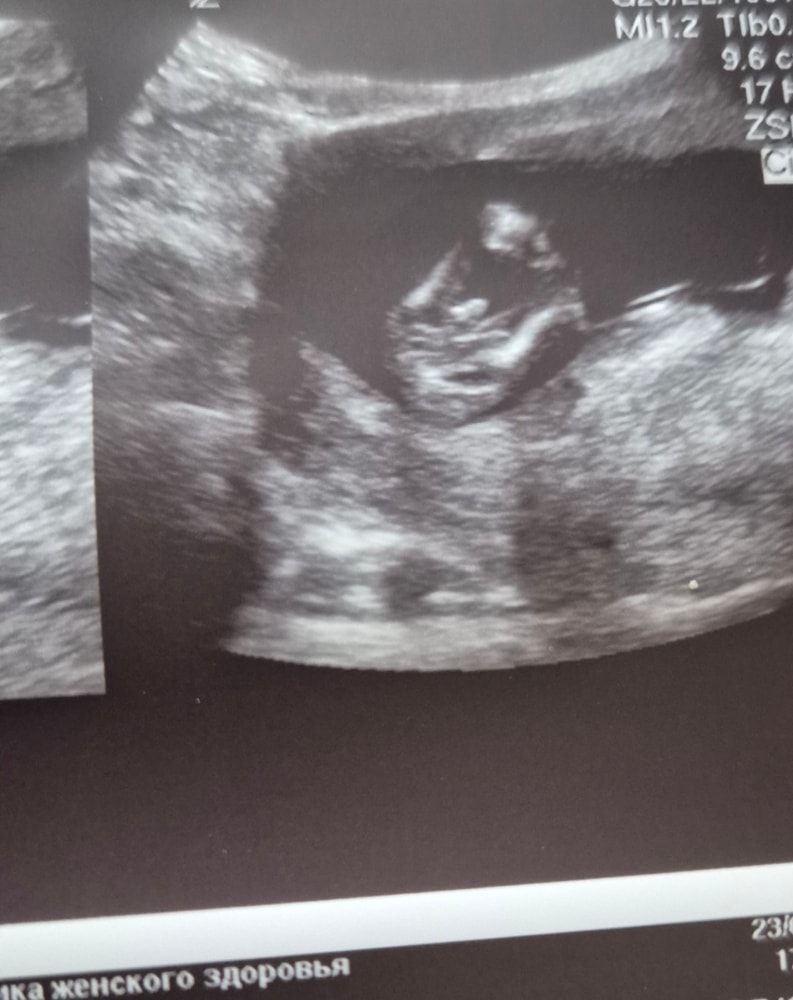

Пол 15 недель

Пол малышаДевочки, узист дал 80% за девочку, но так как матка тонусит, ножки сжаты, оставил 20% на мальчика )

Как вы считаете? Девочка?

У кого есть фото примерно на этом сроке с такого ракурса, покажите пожалуйста, и напишите пол)